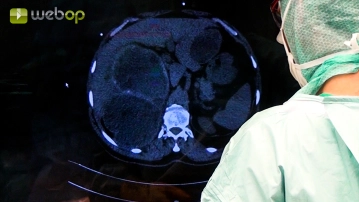

Befunderhebung; Adhäsiolyse; Freipräparation der extrahepatischen Perizyste im linken Leberlappen

Toneinstellungen Typischerweise zeigen die Zysten massive Adhäsionen zur Umgebung. Zunächst werden die Adhäsionen der linksseitigen Zyste zum Omentum abpräpariert. Ein akzidentelles Eröffnen der Zysten muss dabei zwingend vermieden werden. Dann zeigt sich, dass die Perizyste am Magenantrum adhärent ist. Diese Verklebungen werden nun kleinschrittig, teilweise unter Setzen von Overholt-Klemmen, gelöst.